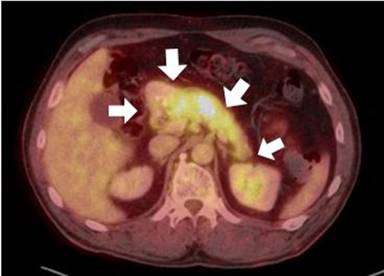

Figure 8. Pre-treatment (a.) and post-corticosteroid therapy (b.) PET maximum intensity projection images show dramatic resolution of IgG4-related hypermetabolic lesions of the salivary/submandibular glands (S), hilar/mediastinal adenopathy (H), bilateral pulmonary lesions (L), pancreas (P), and portacaval and para-aortic adenopathy (A). The IgG4-related cholecystitis (G) has been resected. |